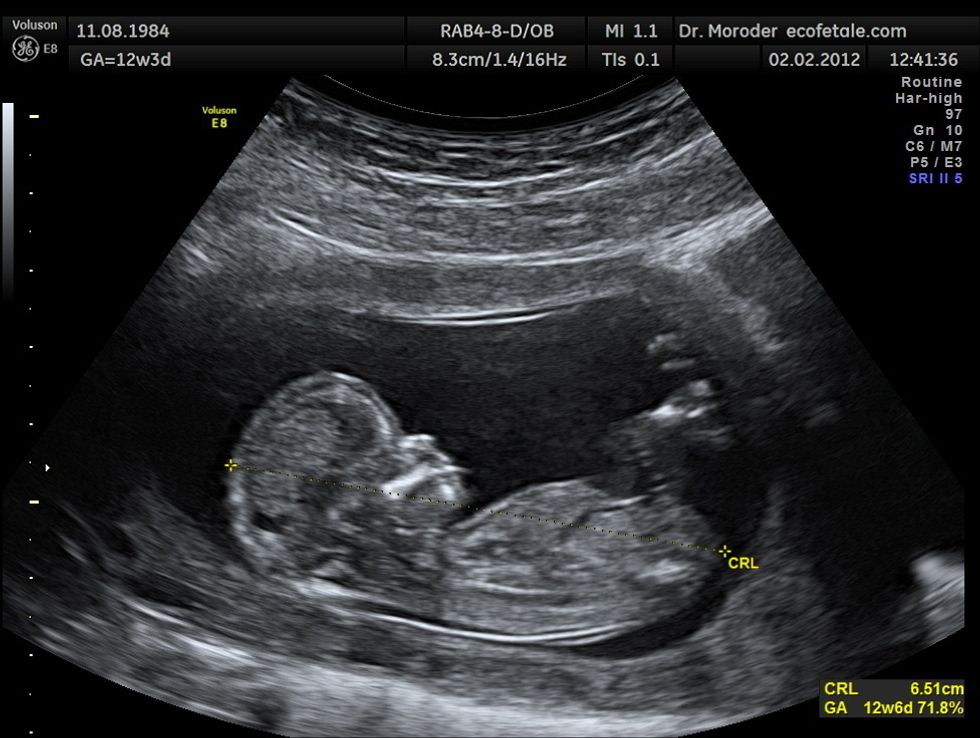

Abby had both kinds of abortions when she was younger, but since she never saw the ultrasound, she didn't think much of it. Later, when she checked her own file and saw it, she was filled with guilt and grief. Many people believe that a fetus is just a clump of cells and tissue. But if you look at an ultrasound, there's a real human baby in there. A baby that deserves to live just as much as you do.

While abortions are usually performed within the first six to twelve weeks (the baby in the ultrasound above is twelve weeks along), they are sometimes allowed to be performed at the last minute. Eight states have laws that permit late-term abortions. It is not shown in the movie, but it is discussed.